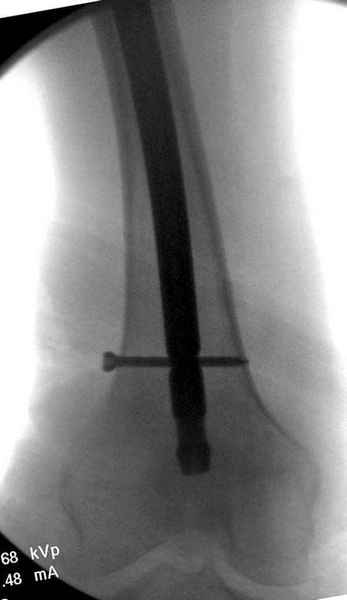

Правильно, ситуация изменилась, как говорят у нас теперь "different animal", надо решать проблему подвертельного перелома. При наличии различных вариантов фиксаторов, включая Страйкер Гамма 3, мы выбрали DePuy Antegrade Trachanteric Nail из-за многовариантности проксимальной фиксации и двойного изгиба. Вводится через вертел под 8 градусным углом, и есть достаточный передний диафизарный изгиб, предупреждающий пенетрацию дистального переднего кортекса.

Кто знает что дальше, мысленно готовы к проксимальной артропластике.